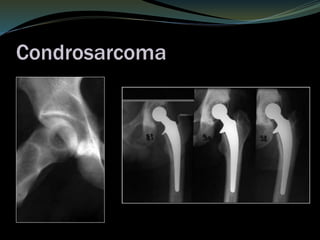

Condrosarcoma

 20 a 25% de los sarcomas óseos

 Adultos y ancianos 40 a 60 años.

 Huesos planos

 cinturas escapular y pélvica

 Diáfisis de los huesos largo.

 De novo

 Transformación maligna de un encondroma

 Osteocondroma

 Dolor

 Intermitente presente durante el reposo.

 Disminución de movilidad

 Inflamación.

 Fracturas patológicas.

Condrosarcoma secundario